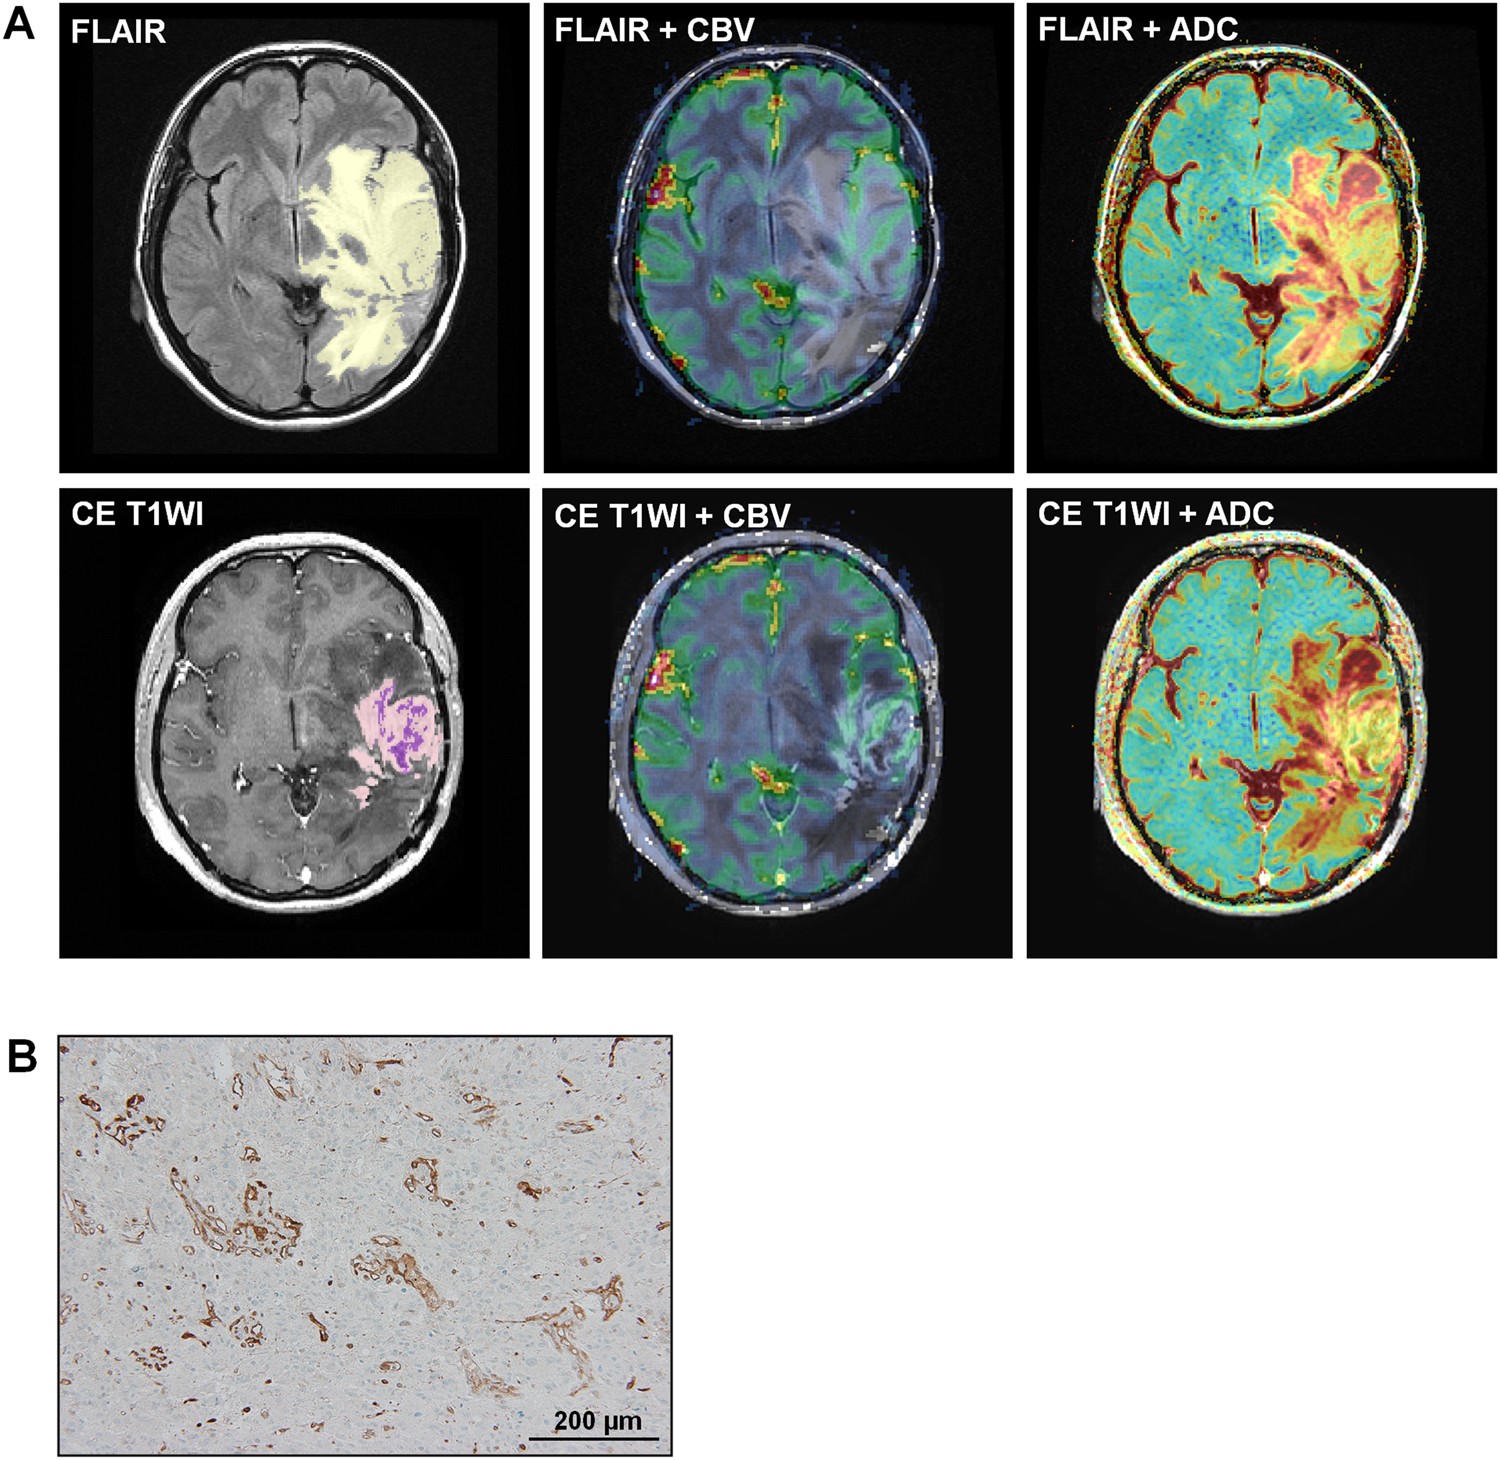

Figure 3

Images in a 43-year-old woman diagnosed with GBM and a low level (17.63) of BCAT1 expression. (A) The tumor showed low nCBV and high ADC values for both FLAIR (Top line, mean nCBV: 1.53, mean ADC: 1481.18 × 10−6 mm2/sec) and contrast enhanced T1W1 (Bottom line, mean CBV: 2.98, mean ADC: 1555.15 × 10−6 mm2/sec). The yellow and light purple ROIs indicate the entire tumor areas on FLAIR and CE T1WI, respectively, and the deep purple ROI represents the necrotic portion within the tumor on CE T1WI. (B) Histology showed a low level of BCAT1 expression.